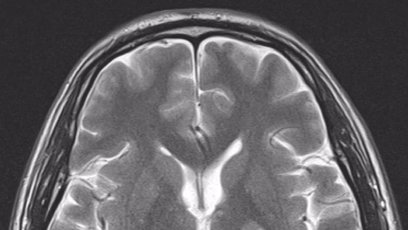

Boj o život! První manažer Ivety Bartošové je v umělém spánku, lékaři se bojí poškození mozku po oživování ZDRAVÍ